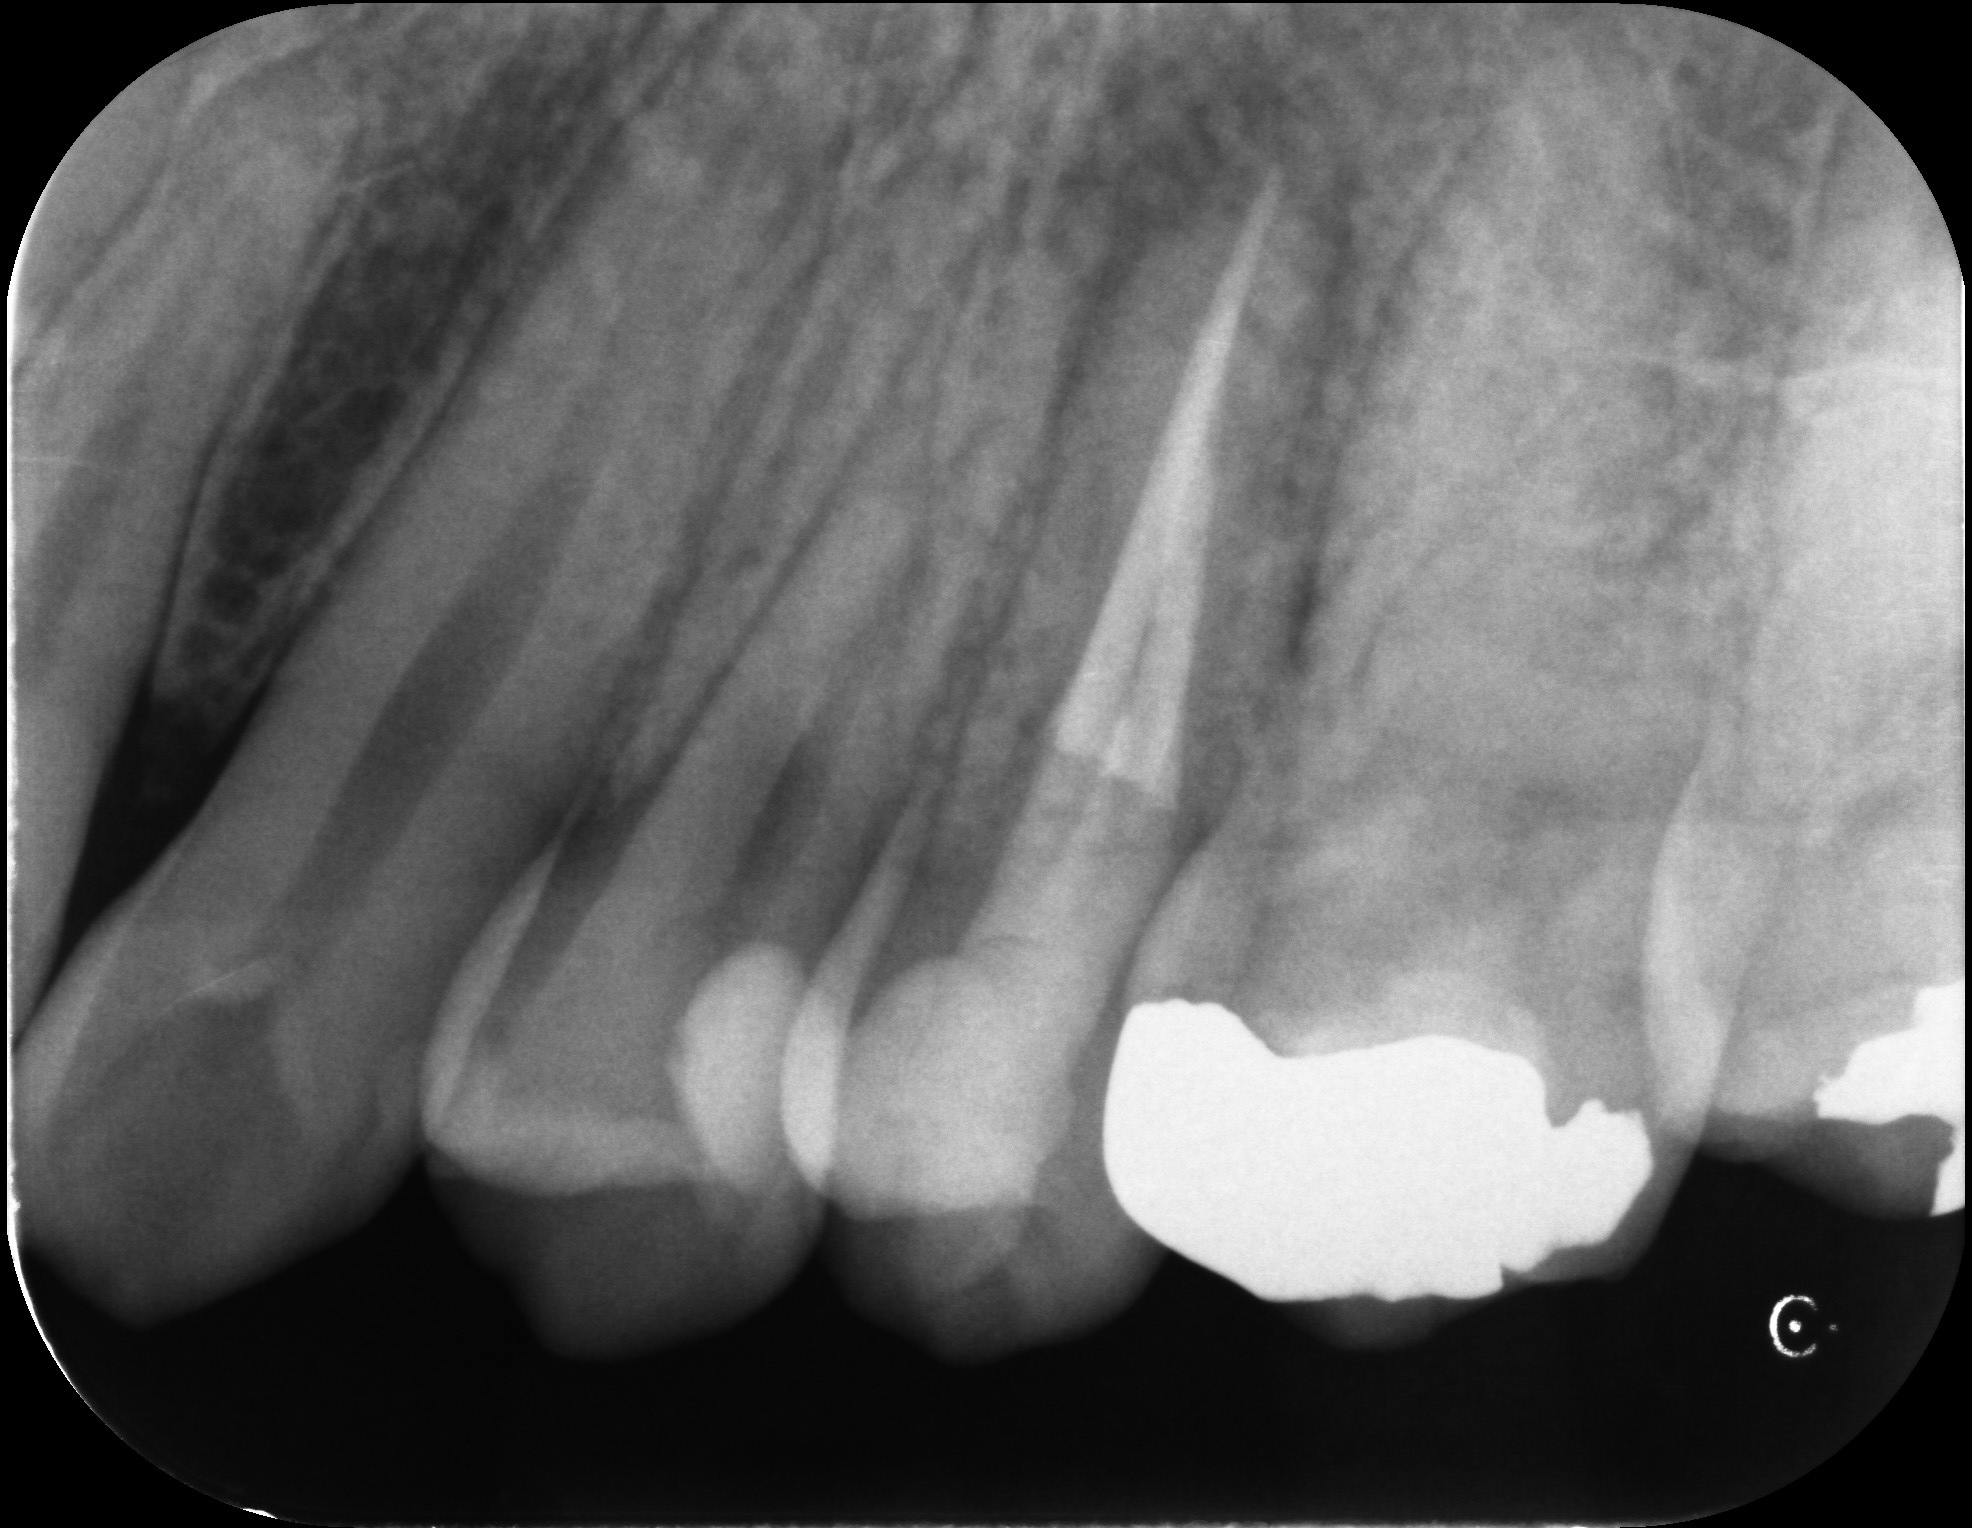

再根管治療で奥歯を残した症例

タップで写真の拡大ができます。

Before

After

主訴

噛むと違和感がある。

治療内容

リトリートメント(再根管治療・大臼歯)

ファイバーポストコア

治療期間

1ヶ月

治療費用

198,000

治療の

リスク

根尖部透過像が完全に消失しない可能性があります。